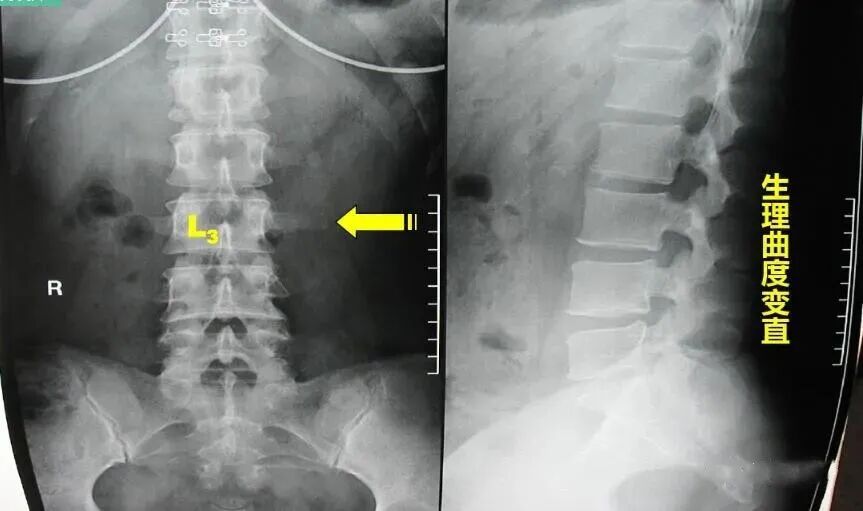

腰椎一共有五个,正常腰椎呈生理性前凸,第3腰椎位于前凸的顶部,腰椎在传导重力时,常是以第3腰椎为其活动中心,故成为腰椎前屈、后伸、左右旋转活动的枢纽。因此,两侧横突所受的牵拉应力最大。在生长发育过程中,受拉应力最大的横突其生长速度也最快。腰三横突位于肋弓与髂嵴之间,横突向后成30度角左右,向前倾斜15度左右,近尖部骨面增厚粗糙。

第三腰椎横突比其他腰椎的后伸曲度大,向侧方延伸最长,位于腰椎中部,两侧腰椎横突联线形成以第三腰椎横突尖为顶点的纵长菱形。第一、二腰椎横突外侧有下部肋骨覆盖,第四、五腰椎横突深居于髂骨内侧,只有第三腰椎横突缺乏肋骨及髂骨保护,因而易受损害。

第三腰椎位于腰前凸曲线之顶点,背阔肌的髂腰部分纤维止于第三腰椎横突,腰大肌的部分肌纤维也止于此处,骶棘肌的一部分肌纤维也止于此,因此,第三腰椎成了腰椎的活动中心,起到了类似接力站的作用,为腰椎屈、伸、侧弯及旋体的枢纽,所受的杠杆作用最大。而第三腰椎横突更是受力点。由于第三腰椎横突较长,以致附着于此处的肌肉、筋膜、韧带能有效地保持脊柱的稳定性及正常的活动。较长的横突又能增强肌肉的杠杆作用,肌肉收缩牵拉机会多,拉力最大,当这些组织异常收缩时,横突末端首当其冲。这种解剖特点构成末端易受损伤的基础,往往因劳损而引起横突末端周围的纤维织炎。横突越长,发病率越高,以单侧多见。